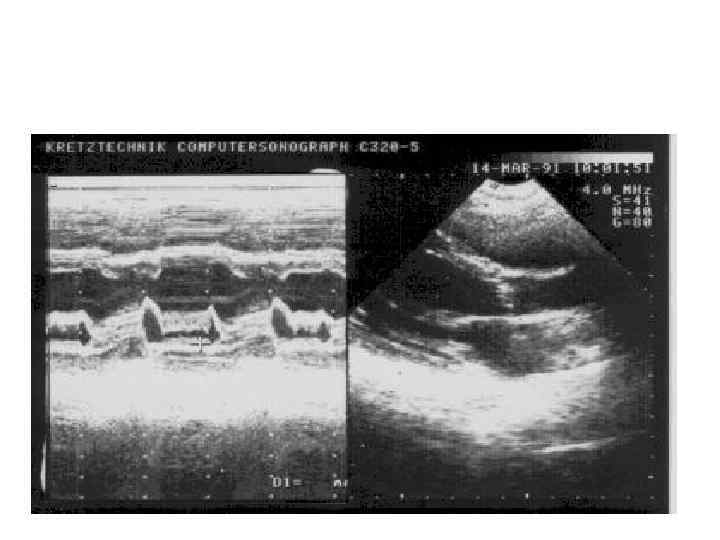

Вегетации на створках митрального клапана

Вегетации на створках аортальных полулуний